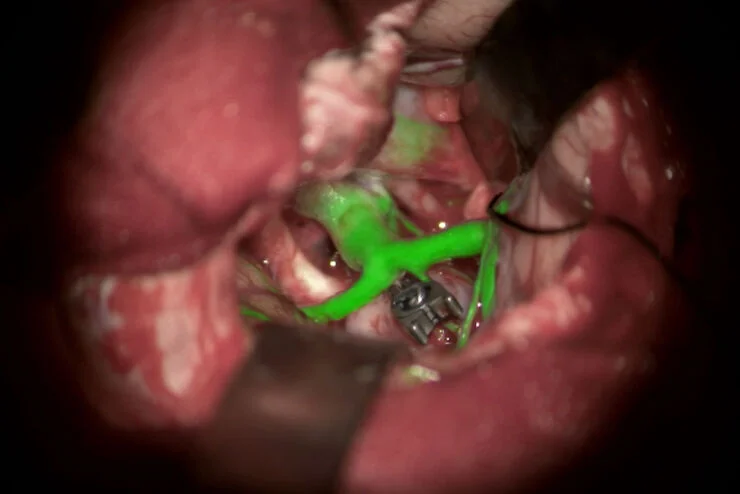

GLOW400

A aplicação de fluorescência GLOW400 AR pode auxiliar na tomada de decisões cirúrgicas mais seguras durante cirurgias suspeitas de glioma de grau III e IV.